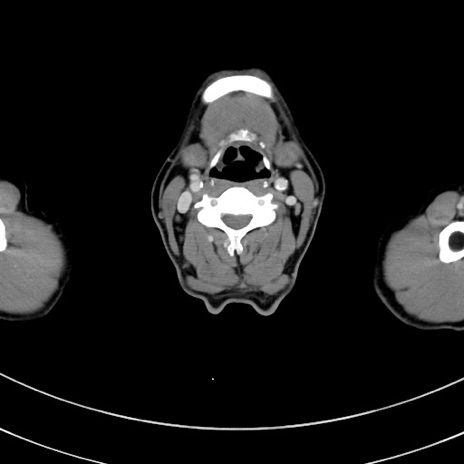

冠状断像